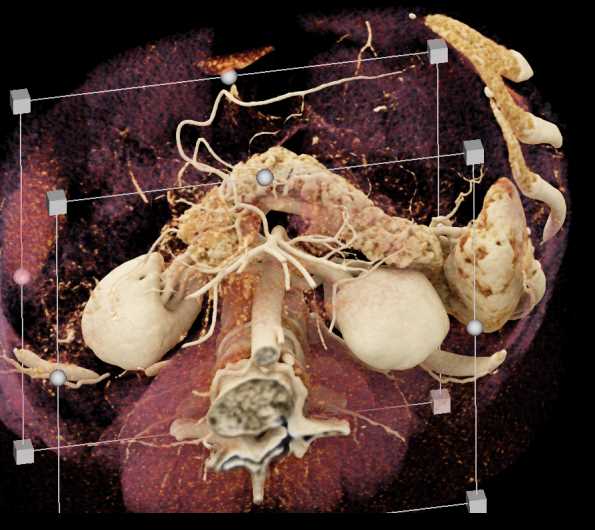

Subtle Neuroendocrine Tumor Body of Pancreas